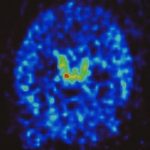

- Post-stroke inflammation: Strokes result in brain neuroinflammation that scientific evidence suggests contributes to the severity of ongoing stroke symptoms.

- TNF’s role: Excess TNF, released by activated microglia in the brain, is a key driver of brain inflammation. By blocking it, etanercept may help reduce neuroinflammation and improve neurological function.